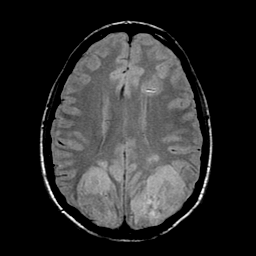

Sarcoma, MR Study #1 mr-pd -- Slice #15

[Home][Help][Clinical] Slice 15